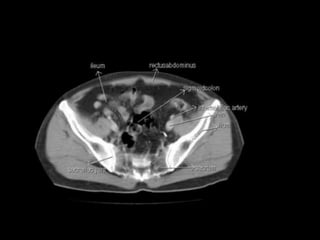

Cross section anatomy of abdominal ct scan

Cross section anatomyof abdominal ct scan